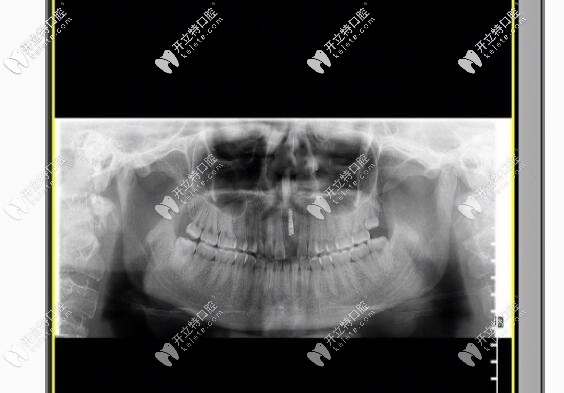

幸好我找對了醫(yī)院和醫(yī)生,醫(yī)生給我的建議是拆除烤瓷牙,換上瑞士iti或瑞典nobel種植牙,幾番考慮之后,我選擇的是瑞士iti種植牙,有利于骨愈合,還不用進行二期手術(shù)什么的,我給忘了,也正好趕上美奧口腔有活動,價格優(yōu)惠的狠喲!

現(xiàn)在已經(jīng)做完種植牙一年多了,就算是近距離交談,也和正常牙沒有差別,我和男朋友都驚呆了!